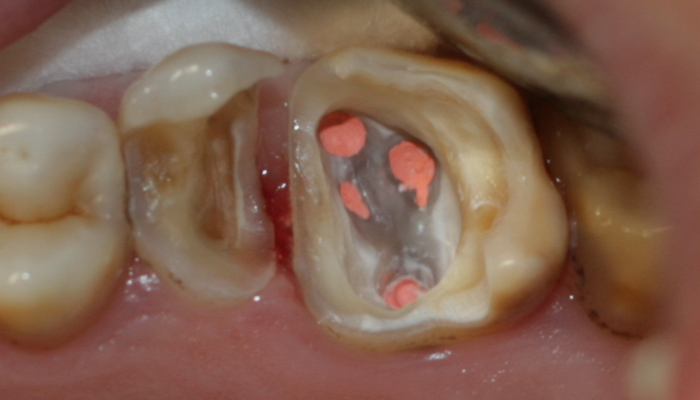

Ендодонтията е раздел от съвременната дентална медицина, който раздел изучава физиологията и патологията на вътрешната част на зъба - пулпна кухина и коренови канали. Названието на раздела идва от старогръцки - ендос - представка за вътрешност и одонтос - зъб. Това е една от научните дисциплини, които претърпяха голямо развитие през последното деситилетие.